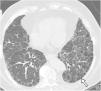

High-resolution computed tomography (HRCT) is the imaging method of choice for the evaluation and diagnosis of interstitial lung diseases because it confirms the presence of lung disease and establishes the correct diagnosis for associated complications. Nevertheless, the definitive diagnosis of these entities requires the imaging findings to be interpreted together with their clinical manifestations and histological confirmation. In this group of diseases, HRCT findings play a fundamental role, being especially important for avoiding unnecessary biopsies. For these reasons, clinicians need to be familiar with the basic radiologic patterns associated with this group of lung diseases: septal, reticular, nodular, ground-glass, cystic, and consolidations. This chapter describes the features of these patterns and ways that they can present, and it reviews some of the most common interstitial lung diseases, emphasizing the predominant radiologic patterns in each of them.

La tomografía computarizada de alta resolución (TCAR) es el método de imagen de elección en la evaluación y el diagnóstico de las EPID, ya que confirma la presencia de enfermedad pulmonar y establece el correcto diagnóstico de las complicaciones asociadas. No obstante, el diagnóstico definitivo de estas enfermedades requiere la concordancia con las manifestaciones clínicas y la comprobación anatomopatológica. Las imágenes radiológicas obtenidas por la TCAR en este grupo de enfermedades tienen un papel fundamental, de especial importancia para evitar la realización de biopsias innecesarias. Por estas razones, el médico clínico debe familiarizarse con los patrones radiológicos básicos asociados a este grupo de enfermedades pulmonares: septal, reticular, nodular, en «vidrio deslustrado», quístico y de condensación. En este capítulo se describen las características y la forma de presentación de estos patrones, y se revisan algunas de las EPID más frecuentes, haciendo hincapié en los patrones radiológicos predominantes en ellas.